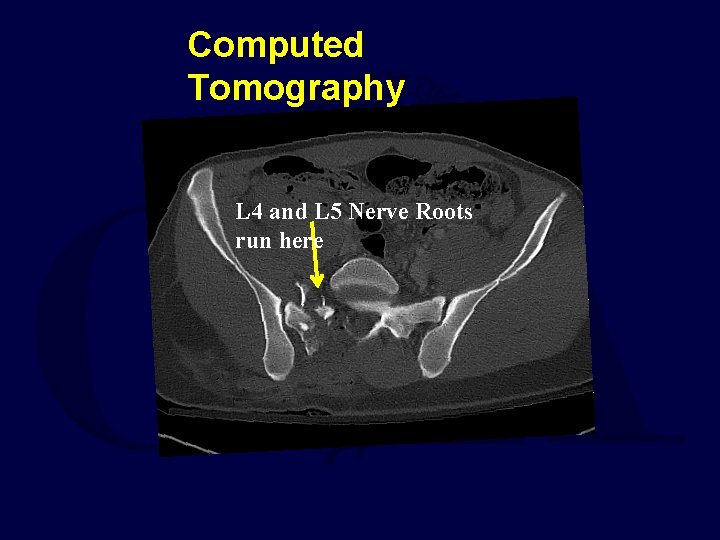

Computed Tomography

Computed Tomography L 4 and L 5 Nerve Roots run here